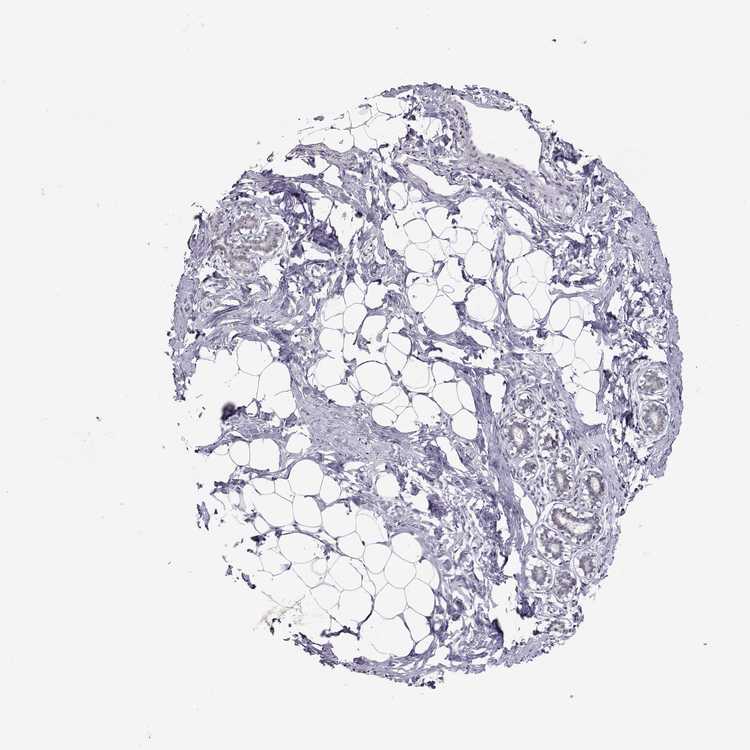

BREAST - Antibody stainingi

Antibody staining in the annotated cell types in the current human tissue is reported as not detected, low, medium, or high, based on conventional immunohistochemistry profiling in selected tissues. This score is based on the combination of the staining intensity and fraction of stained cells.

Each image is clickable and will lead to virtual microscopy that enables deeper exploration of all samples and also displays staining intensity scores, fraction scores and subcellular localization as well as patient and tissue information for each sample.

Antibody HPA014348

Adipocytes Not detected

Glandular cells Low

Myoepithelial cells Not detected